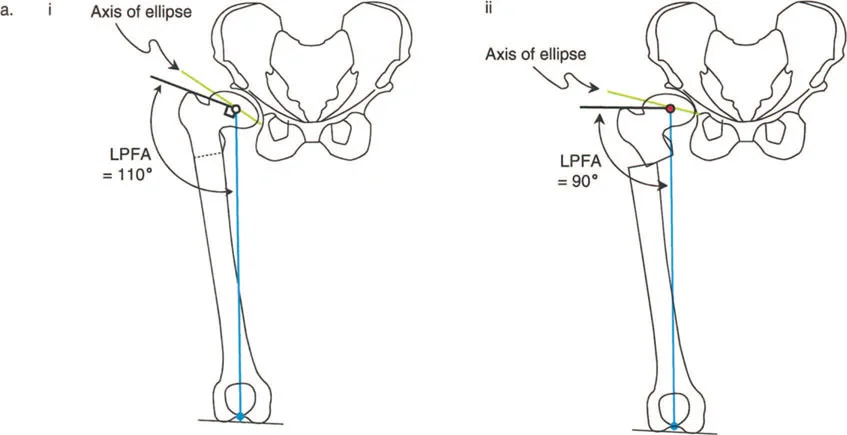

تعتبر الأشعة السينية (X-rays) هي الأداة التشخيصية الأساسية والأكثر أهمية في تقييم تشوهات مفصل الورك. يتم أخذ صور متعددة للمفصل من زوايا مختلفة (مثل الأمامي الخلفي والجانبي) لتمكين الجراح من:

- قياس الزوايا: تحديد الزاوية بين عنق وجسم الفخذ (NSA)، والزاوية الميكانيكية لعظم الفخذ القريب (MPFA)، والزاوية الجانبية لعظم الفخذ القريب (LPFA). هذه القياسات حاسمة لتخطيط الجراحة.

- تقييم شكل العظام: تحديد وجود كسع الورك أو فحج الورك، أو تضخم المدور الكبير، أو رأس فخذ بيضاوي الشكل.

- رأس الفخذ البيضاوي: في بعض حالات كسع الورك، قد يكون رأس الفخذ بيضاوي الشكل. يهدف قطع العظم الفحجي في هذه الحالات إلى جعل المحور الطويل للقطع البيضاوي أكثر أفقية لزيادة مساحة تحمل الوزن وتقليل الضغط على المفصل.

صور بالأشعة السينية لحالة كسع الورك مع رأس فخذ بيضاوي، توضح كيفية تصحيح اتجاه المحور البيضاوي بقطع عظم فحجي لتحسين توزيع الحمل.